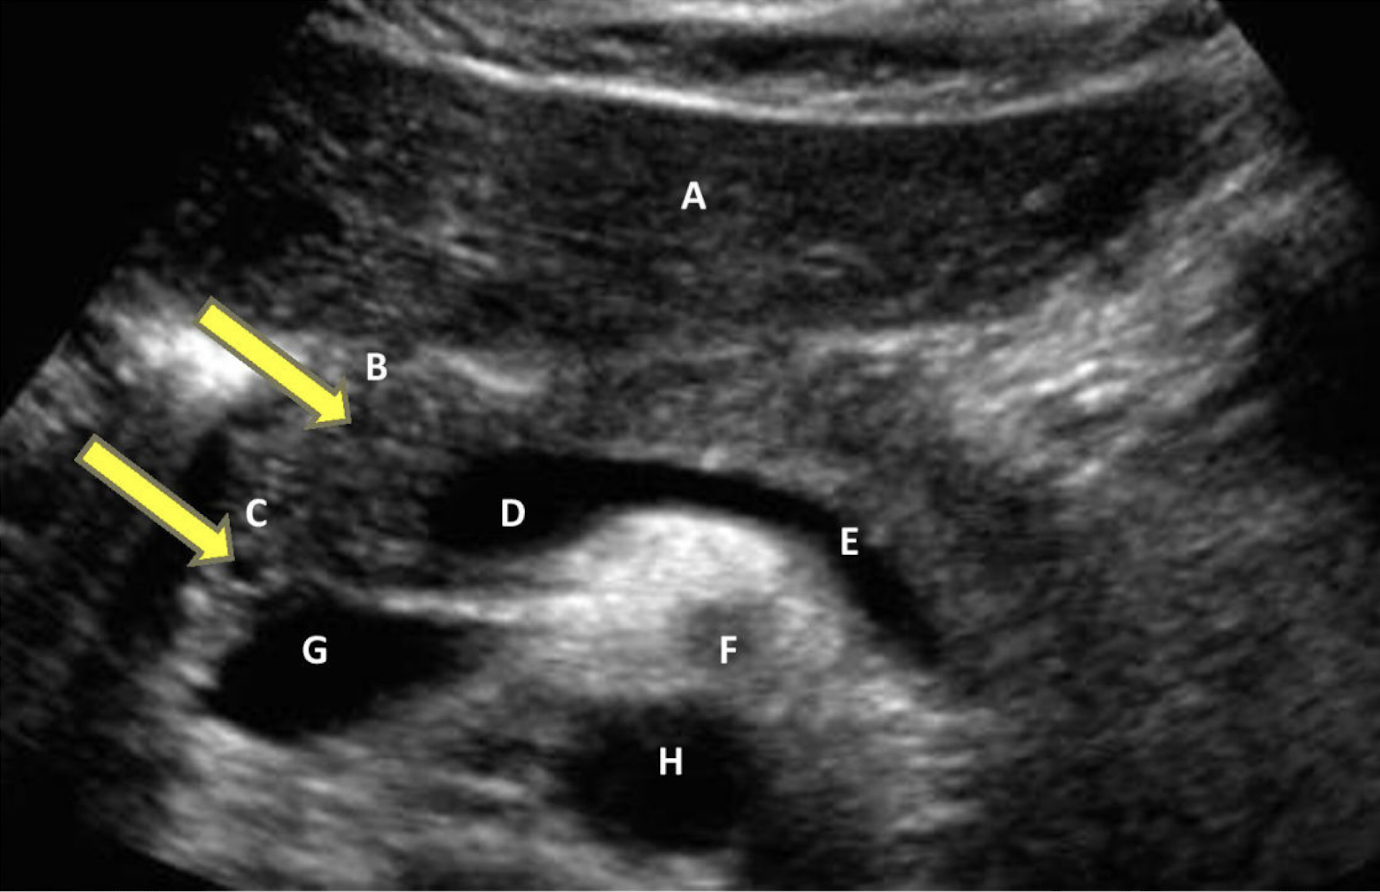

identify all structures

A) left liver lobe

B) gastroduodenal artery

C) common bile duct

D) Main portal confluence

E) Splenic vein

F) SMA

G) IVC

H) Aorta